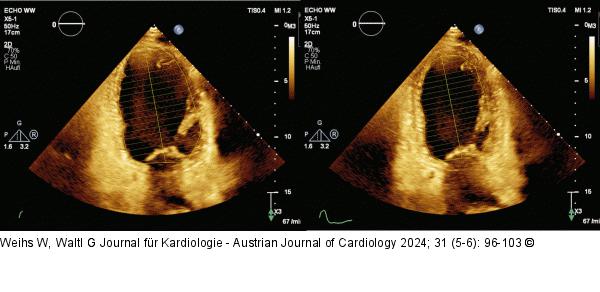

Abbildung 4: Echo Messung der linksventrikulären Volumina und EF nach der Simpson-Methode. CAVE: Von Mitralring zu Mitralring wird jeweils eine Gerade gezogen (und damit ein kleiner Anteil des linken Vorhofs mitgemessen). Die Papillarmuskel werden von der Messung ausgeschlossen/abgeschnitten. |

Abbildung 4: Echo

Messung der linksventrikulären Volumina und EF nach der Simpson-Methode. CAVE: Von Mitralring zu Mitralring wird jeweils eine Gerade gezogen (und damit ein kleiner Anteil des linken Vorhofs mitgemessen). Die Papillarmuskel werden von der Messung ausgeschlossen/abgeschnitten. |